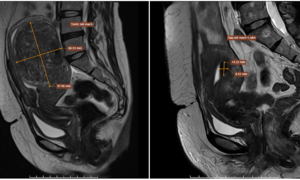

A large uterine fibroid caused Chi Hoa seven years of secondary infertility, requiring surgery combined with in vitro fertilization to have a second child.

Minh, 38, successfully underwent surgery using the Da Vinci Xi robot to remove a uterine fibroid located in the broad ligament, a challenging surgical site.